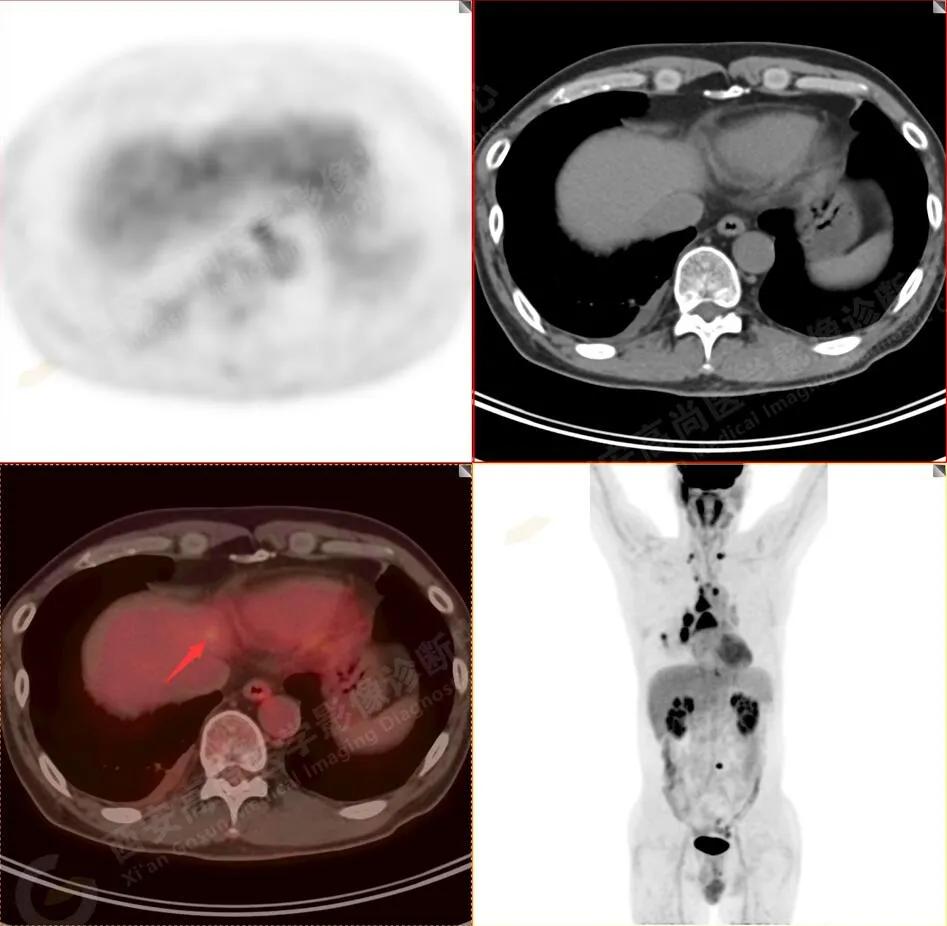

肝内可疑转移瘤

6.肝内小结节,考虑转移可能性大,建议MR增强扫描。

肝内多发转移瘤

4.肝S4、8段团块状及结节状低密度病变,以S4段病变为著,呈不同程度FDG代谢异常增高,考虑为肝多发转移。